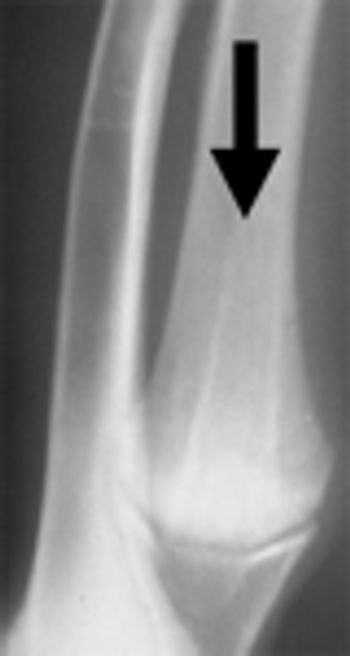

OCD of the hock occurred bilaterally in 42% of the reported cases. The lateral trochlear ridge is involved in 25% of the cases and the medial trochlear ridge in 75% of the cases.